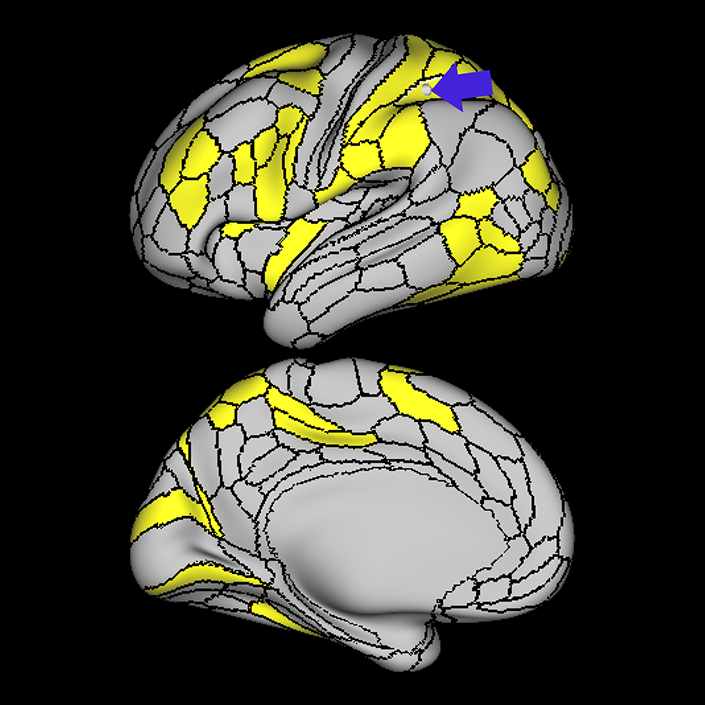

Connectome Guide

Language Network

Why we think this network is worth considering in decision making:

Disturbances of language have been linked to anatomic disruption of the human language network architecture for nearly 150 years.

Evidence that this network is responsible for useful function in humans:

While details regarding its exact organization are still in refinement, the basic details regarding the anatomy of the human language system have been non-controversial for many decades, and there is a long and robust history of using models of the language system in clinical decision-making spanning back a very long time.

Exploring the language organization in the brain began in the mid-19th century with Broca’s and Wernicke’s studies on patients with defined brain injuries and lesions in the mid-19th century.1,2 Further studies identified a neural tract, the arcuate fasciculus, for connecting Broca’s and Wernicke’s areas being one of the major components of language processing in humans.3 Later on, more studies confirmed and expanded these findings using additional techniques such as cortical intraoperative mapping,4 and subcortical mapping,5 and neuroimaging using DTI and fMRI. Using DTI, Rilling et al., (2008) found a noticeable temporal projection of arcuate fasciculus that is much smaller or absent in non-human primates.6 Further studies reported a strong left lateralization of arcuate fasciculus in humans.7

Additional invasive tests have been described to study impact on networks for clinical decision making. Historically injecting sodium amytal into one carotid artery (Wada Test) has been the gold standard for finding out the language lateralization in the brain.8 Studies found a very strong correlation between Wada test and language lateralization.9 More recently, similar findings have emerged using non-invasive neuro-imaging techniques. One study reported fMRI superiority over Wada test predicting postoperative language function in patients when fMRI and Wada test are not consistent with each other.10 Moreover, a recent guideline by the American Academy of Neurology suggested fMRI may be considered as a replacement of Wada test in epilepsy.11

Consequences of damage to this network:

Evidence that damaging this network causes neurological decline.

Several studies demonstrated aphasic impairment as a result of damage to this network in stroke patients, epilepsy patients, and tumor patients.12,13,14

Lately, speech network has been successfully mapped using rs-fMRI in an aphasic patient with left temporal tumor even in the absence of cognitive function. In the study, patient was scanned before and after a seizure that causes aphasia for several days.15 In aged patients it was found that higher functional connectivity in the left language areas associated with higher scores in behavioral tests, this finding suggests a role for functional preservation in these areas.16